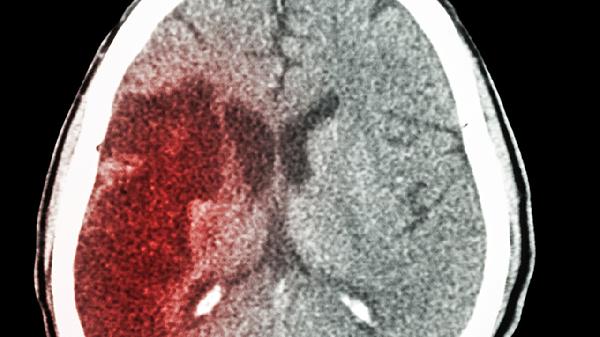

产伤或早产儿脑室内出血后,血块机化可能造成蛛网膜下腔粘连,影响脑脊液循环。此类患儿多有窒息抢救史,需定期监测头围和颅压,严重时需行脑室镜下粘连松解术。